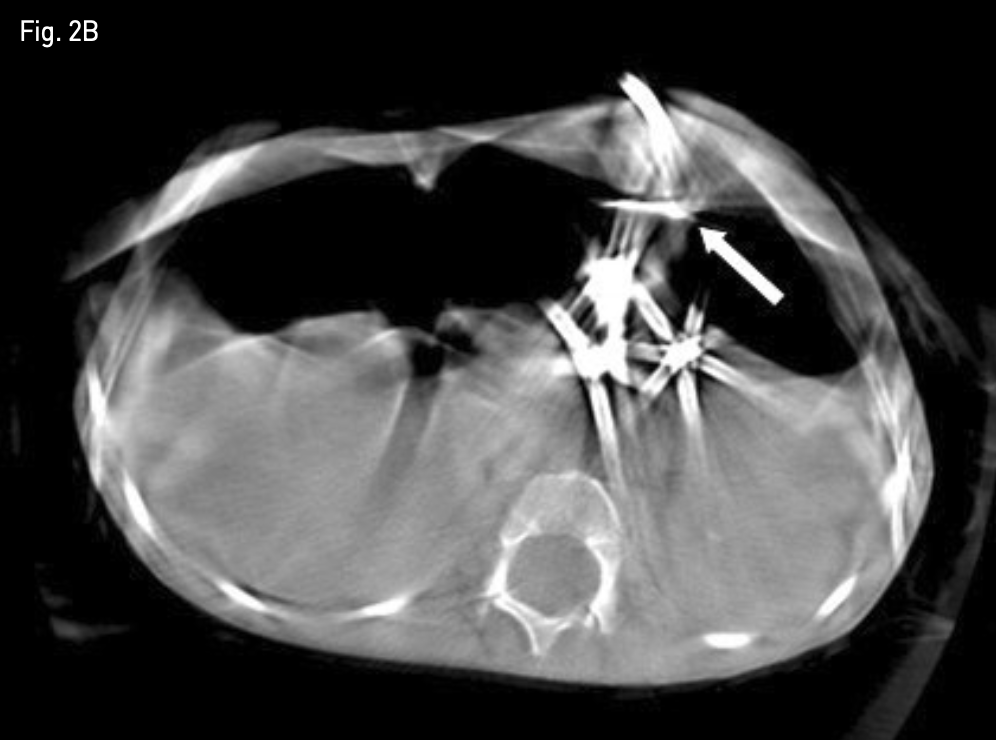

Fig. 1B

Non-contrast axial abdominal CT image, obtained 1 day after percutaneous radiologic gastrostomy shows significant gap between anterior abdominal wall and anterior wall of the stomach with first T-fastener (white arrow).

Fig. 2B

Cone beam CT image shows significant gap between anterior abdominal wall and anterior wall of the stomach with first T-fastener (white arrow).